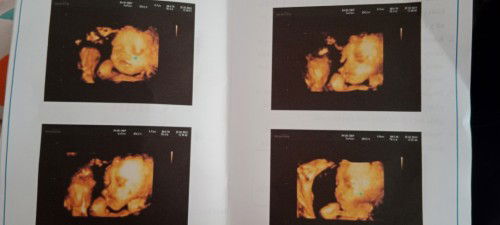

e 29 tuần bé đc 1kg160 ạ 😪